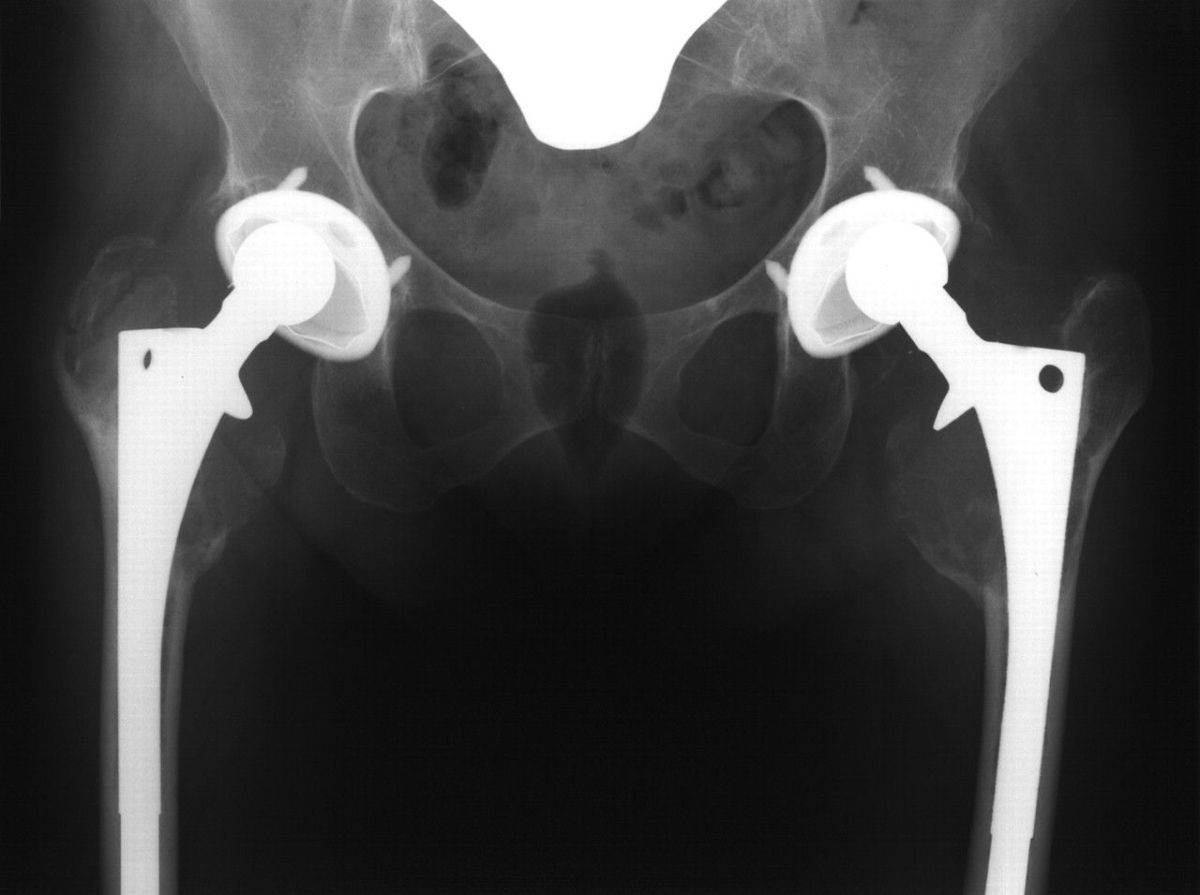

:max_bytes(150000):strip_icc()/x-ray-illustration-of-hip-replacement-1254389829-281a949198324333972a407cc2e90760.jpg)